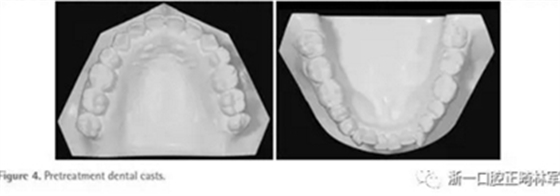

面部照片顯示,患者為凸面型,鼻唇時頦肌緊張(Figure 3)??趦?nèi)檢查顯示雙側(cè)第二前磨牙間開合(Figures3 and 4)。覆合覆蓋分別為-3.5mm和+1.2mm。正面觀,上下牙列中線與面部中線一致。雙側(cè)磨牙II類關(guān)系,下前牙區(qū)中度擁擠。